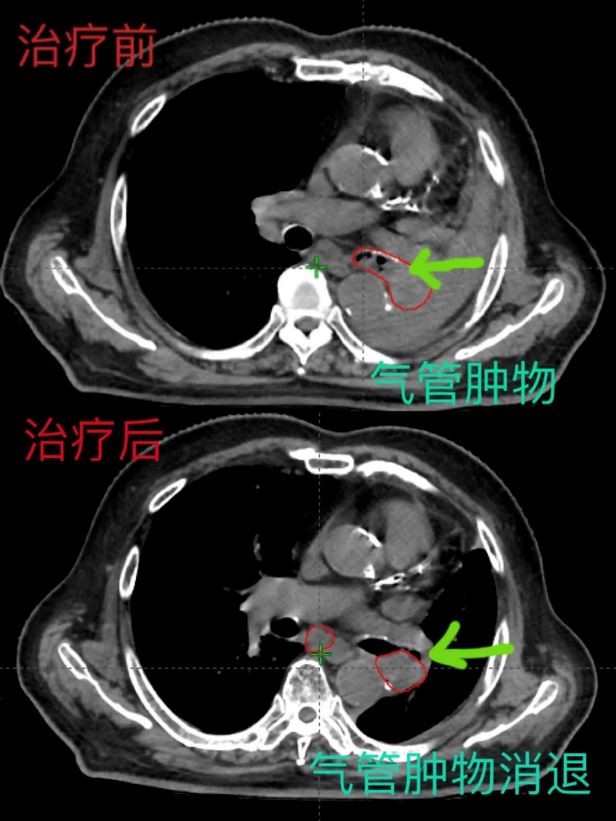

以現(xiàn)代影像技術(shù)與放療技術(shù)緊密結(jié)合,通過精準(zhǔn)的腫瘤定位,精準(zhǔn)的計(jì)劃設(shè)計(jì)、精準(zhǔn)的劑量計(jì)算,經(jīng)過放射治療10次后,復(fù)查胸部CT示:左肺門腫塊明顯縮小,左主支氣管內(nèi)腫物明顯消退,左肺膨脹良好,縱膈回位。左肺呼吸功能恢復(fù)。放射治療療效顯著,患者癥狀明顯改善,有效的減輕了患者的痛苦,提高了生活質(zhì)量。

隨著放療技術(shù)不斷進(jìn)步,先進(jìn)設(shè)備的引進(jìn)與使用,佳木斯大學(xué)宏大醫(yī)院精準(zhǔn)放療領(lǐng)域取得了突破性進(jìn)展,對(duì)手術(shù)風(fēng)險(xiǎn)較大或耐受性較差的患者,在保護(hù)好周圍器官的前提下,實(shí)現(xiàn)腫瘤的診斷、扣模、CT定位、靶區(qū)勾畫、治療計(jì)劃設(shè)計(jì)和精準(zhǔn)照射的一體化,為患者提供科學(xué)、有效、安全的診療方案,并定期對(duì)病人的治療反饋進(jìn)行質(zhì)量評(píng)估和優(yōu)化,不斷修正診療模式,實(shí)現(xiàn)精確定位、精確計(jì)劃、精確治療。